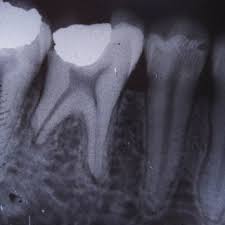

External root resorption treatment. If a dentist is able to spot the external symptoms and remove the cells causing damage in time you may not require any further dental care. Root resorption has been defined as the loss of dental hard tissue as a result of osteoclastic cell action 1 and can occur on both external and internal surfaces. If you can access then treatment with geristore or similar and possibly TCA for 1-4 minutes to remove tissue fragments.

The therapeutic measures which can regulate clastic activity include endodontic treatment the use of specific anticlastic agents such as Ledermix paste non-specific necrobiotic agents such as calcium hydroxide and trichloracetic acid surgery or root surface conditioners. External root resorptions are processes in which the loss of cementoblasts occurs causing the mineralized surfaces to be susceptible to the action of clastic cells. If you look at the tooth from the coronal view youll notice the location of the resorption is a little improved making it easy to understand why we call it external cervical resorption.

However if more of the tooth structure has been affected a filling or root canal therapy might be the treatment of choice. Although it is predominantly detected by radiography in some cases root resorption may be identified by clinical symptoms such as pain swelling and mobility of the tooth. Patient was willing to try to save the tooth and took the second option. Sometimes it may be possible to repair the damage to the tooth but in some cases the only solution is to extract the. A second opinion may be necessary. In cases where the resorptive process is already established root canal treatment can arrest the resorption and encourage hard tissue repair. External root resorptions are processes in which the loss of cementoblasts occurs causing the mineralized surfaces to be susceptible to the action of clastic cells. External resorption can be misdiagnosed. External cervical resorption treatment options vary depending on the severity of the situation.

External Resorption Treatment ConsiderationsPrognosis Favorable Questionable Unfavorable External Resorption Minimal loss of tooth structure Located cervically but above the crestal bone The lesion is accessible for repair Apical root resorption associated with a tooth exhibiting pulp necrosis and apical pathosis Minimal impact on restorability of tooth. What is the treatment for dental resorption. The therapeutic measures which can regulate clastic activity include endodontic treatment the use of specific anticlastic agents such as Ledermix paste non-specific necrobiotic agents such as calcium hydroxide and trichloracetic acid surgery or root surface conditioners. If you look at the tooth from the coronal view youll notice the location of the resorption is a little improved making it easy to understand why we call it external cervical resorption. If a dentist is able to spot the external symptoms and remove the cells causing damage in time you may not require any further dental care. Root canal crown gum surgery tooth removal extraction. The treatment of root resorption is basically root and or periodontal endodontic treatment depending on the.